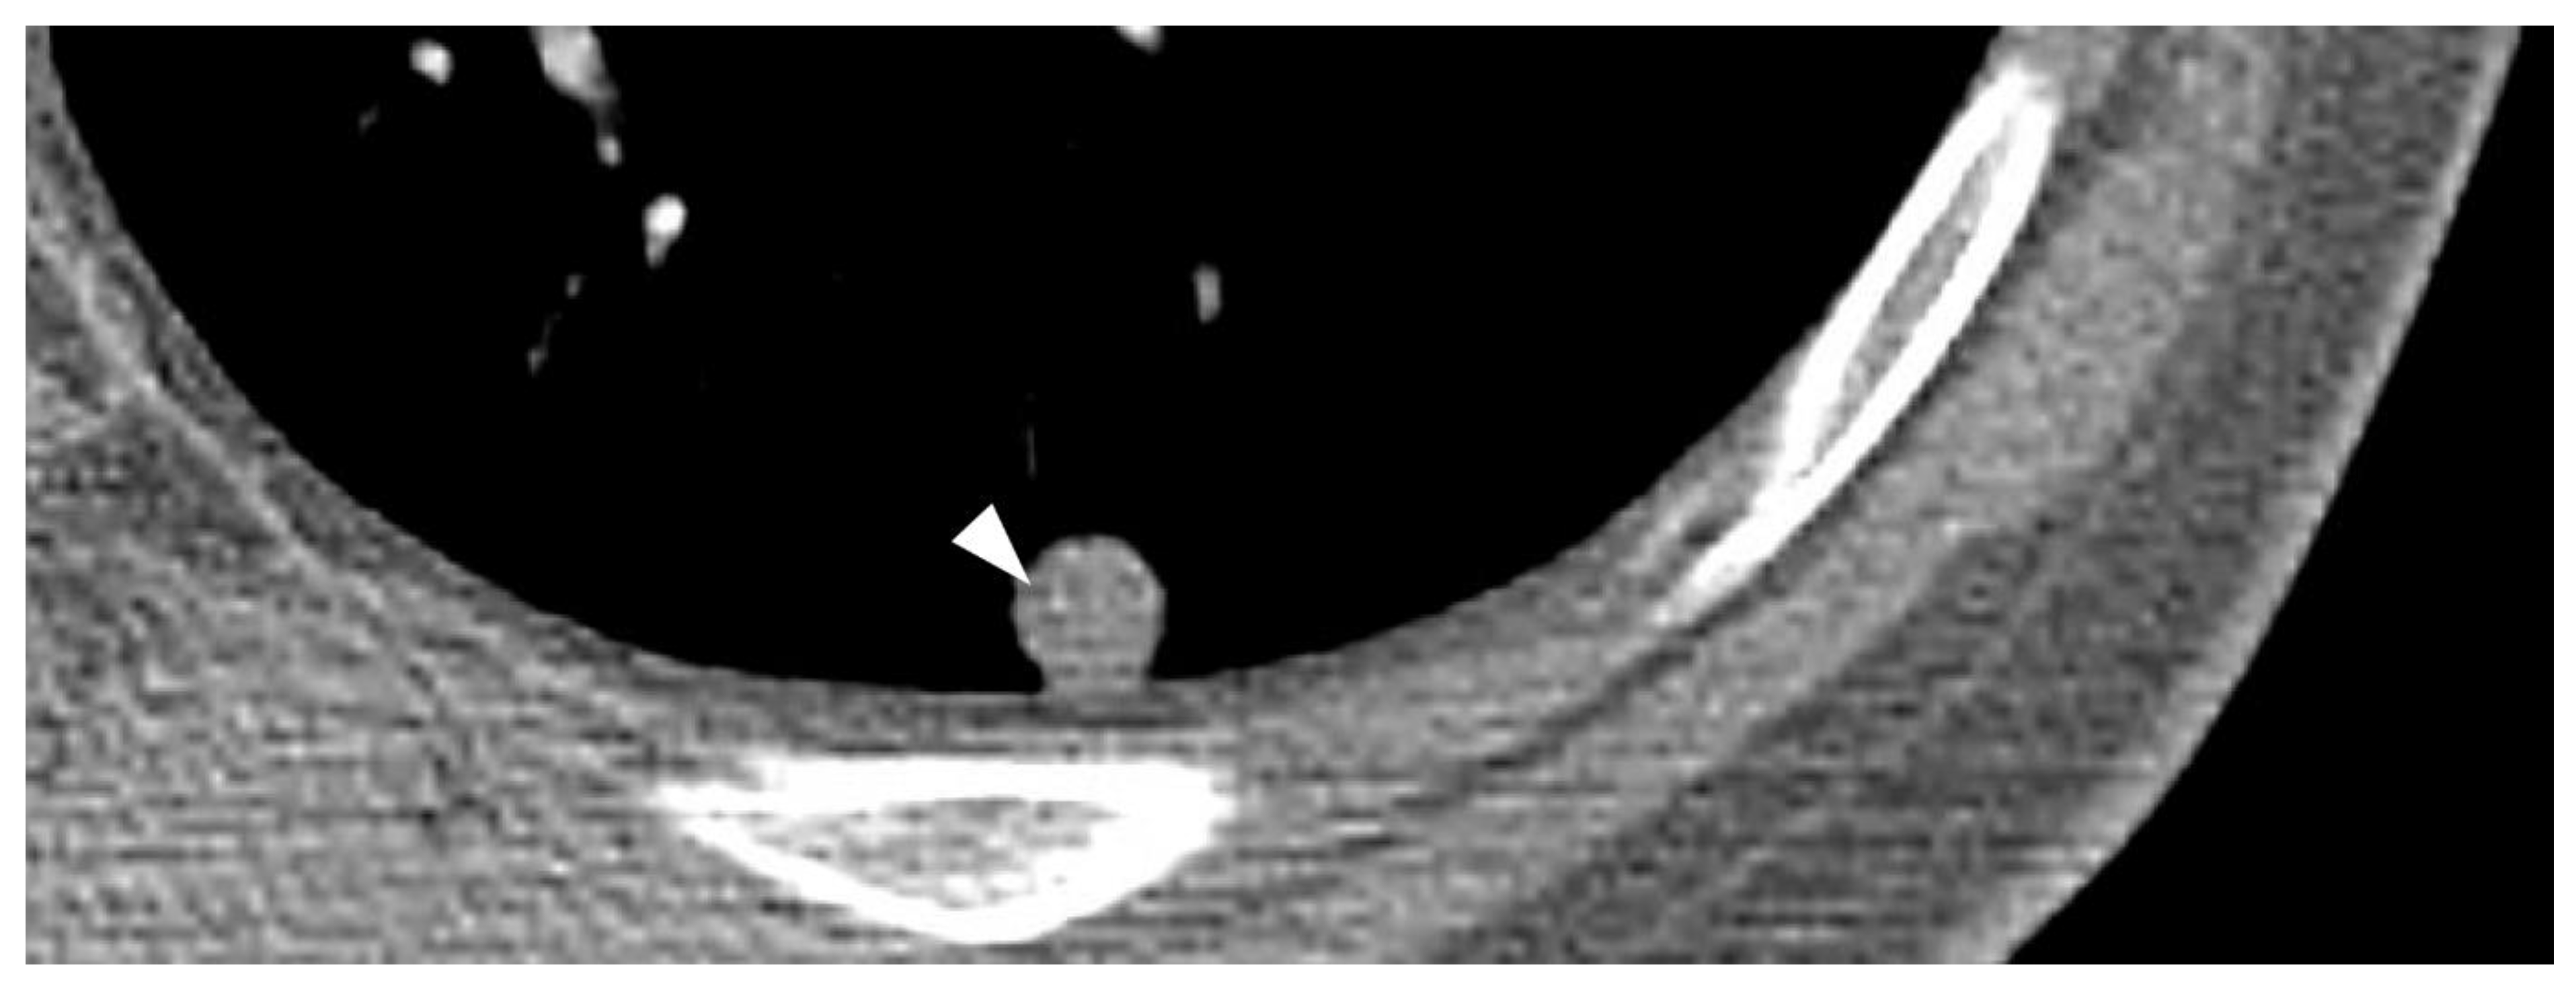

2.2. Computed Tomography (CT)

| Imaging features | Intratumoral hemorrhage (fluid-fluid levels) | Poor |

| Calcification | Favorable |